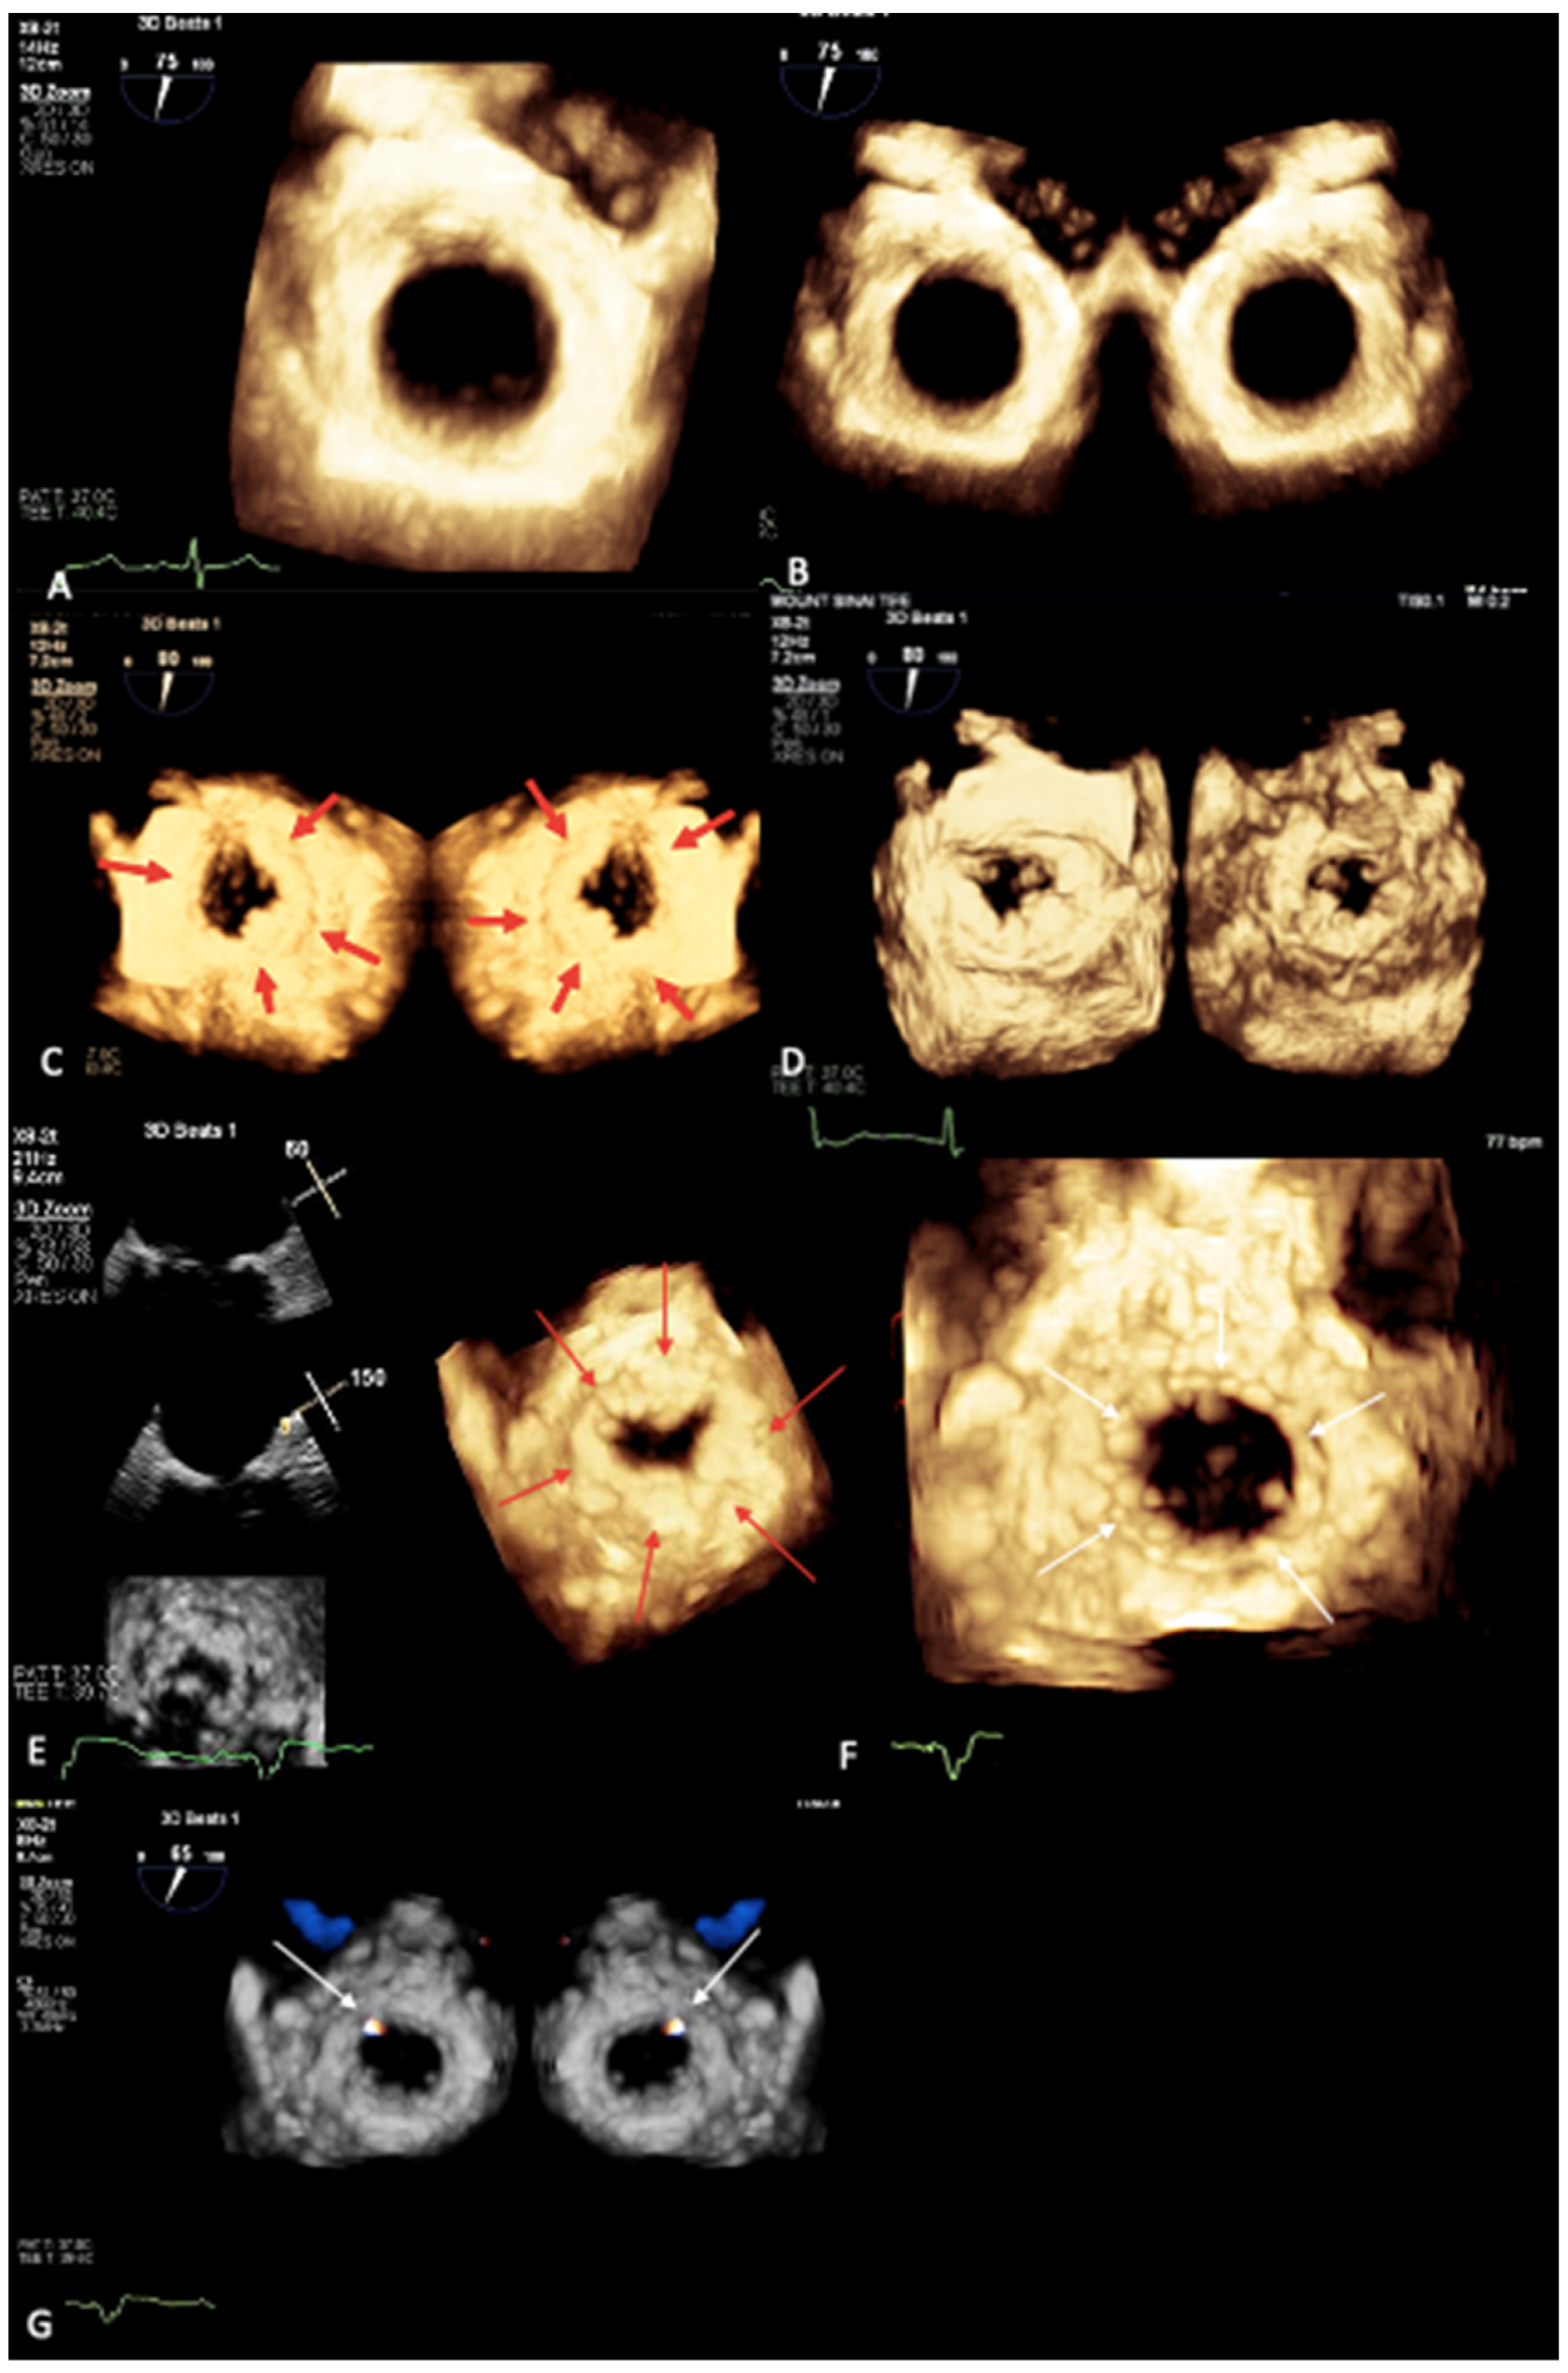

2. Mitral Annular Calcification Imaging

3. Novel 3D Echocardiographic Technique for MAC

4. Maximal Intensity Projection Map Applications

- Prandi, F.R.; Anastasius, M.O.; Zhang, L.; Tang, G.H.; Moreno, P.R.; Romeo, F.; Barillà, F.; Sharma, S.; Kini, A.; Lerakis, S. Novel Three-Dimensional Transesophageal Echocardiographic Method for Mapping Mitral Annular Calcifications. J. Am. Soc. Echocardiogr. 2022, 35, 1004–1005. [Google Scholar] [CrossRef] [PubMed]

- Prandi, F.R.; Dangas, G.D.; Kini, A.; Romeo, F.; Suleman, S.; Khera, S.; Tang, G.H.; Sharma, S.; Lerakis, S. Intraprocedural Mapping of the Mitral Calcium for Positioning and Deployment of Transcatheter Valve-in-Mitral Annular Calcification. JACC Cardiovasc. Interv. 2022, 15, 2341–2343. [Google Scholar] [CrossRef] [PubMed]